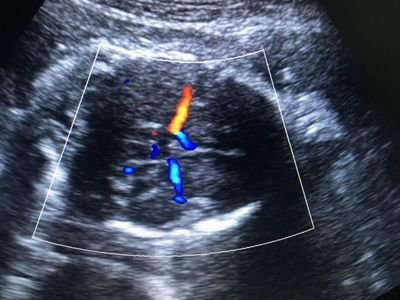

所谓彩超,就是彩色多普勒血流成像,英文缩写就是CDFI。简单的说,就是在二维显像的基础上,以实时彩色编码显示血流的方法,把向着探头方向流动的血流,显示为红色,把远离探头方向流动的血流,显示为蓝色。

而且,不管是红色还是蓝色,颜色越亮,代表血流的速度越快。

机灵的小伙伴可能已经又总结出了一点:哦~原来红色和蓝色代表的是血流方向,不是动脉和静脉呀!

但是我们超声医生检查的时候,并不是一直都需要看彩色血流信号的,而几乎都是先看二维超声上的解剖结构,当找到需要查看血流信号的兴趣区时,我们就会加上CDFI,这个时候你再看屏幕,它就成了彩色的啦!

一句话,彩超就是二维超声和血流信号的结合,大大提高了超声诊断率哟!